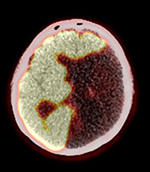

75 year-old man with history of lung cancer in remission. Axial CT (A), PET (B), PET-CT fused (C) and MIP images (D) demonstrate large area of encephalomalacia involving the left cerebral hemisphere in the territory of middle cerebral artery with expected decreased FDG activity. Decreased FDG activity in the contralateral right cerebellar hemisphere on MIP image is consistent with cerebellar diaschisis. |

| 75 year-old man with history of lung cancer in remission. Axial CT (A), PET (B), PET-CT fused (C) and MIP images (D) demonstrate large area of encephalomalacia involving the left cerebral hemisphere in the territory of middle cerebral artery with expected decreased FDG activity. Decreased FDG activity in the contralateral right cerebellar hemisphere on MIP image is consistent with cerebellar diaschisis. |